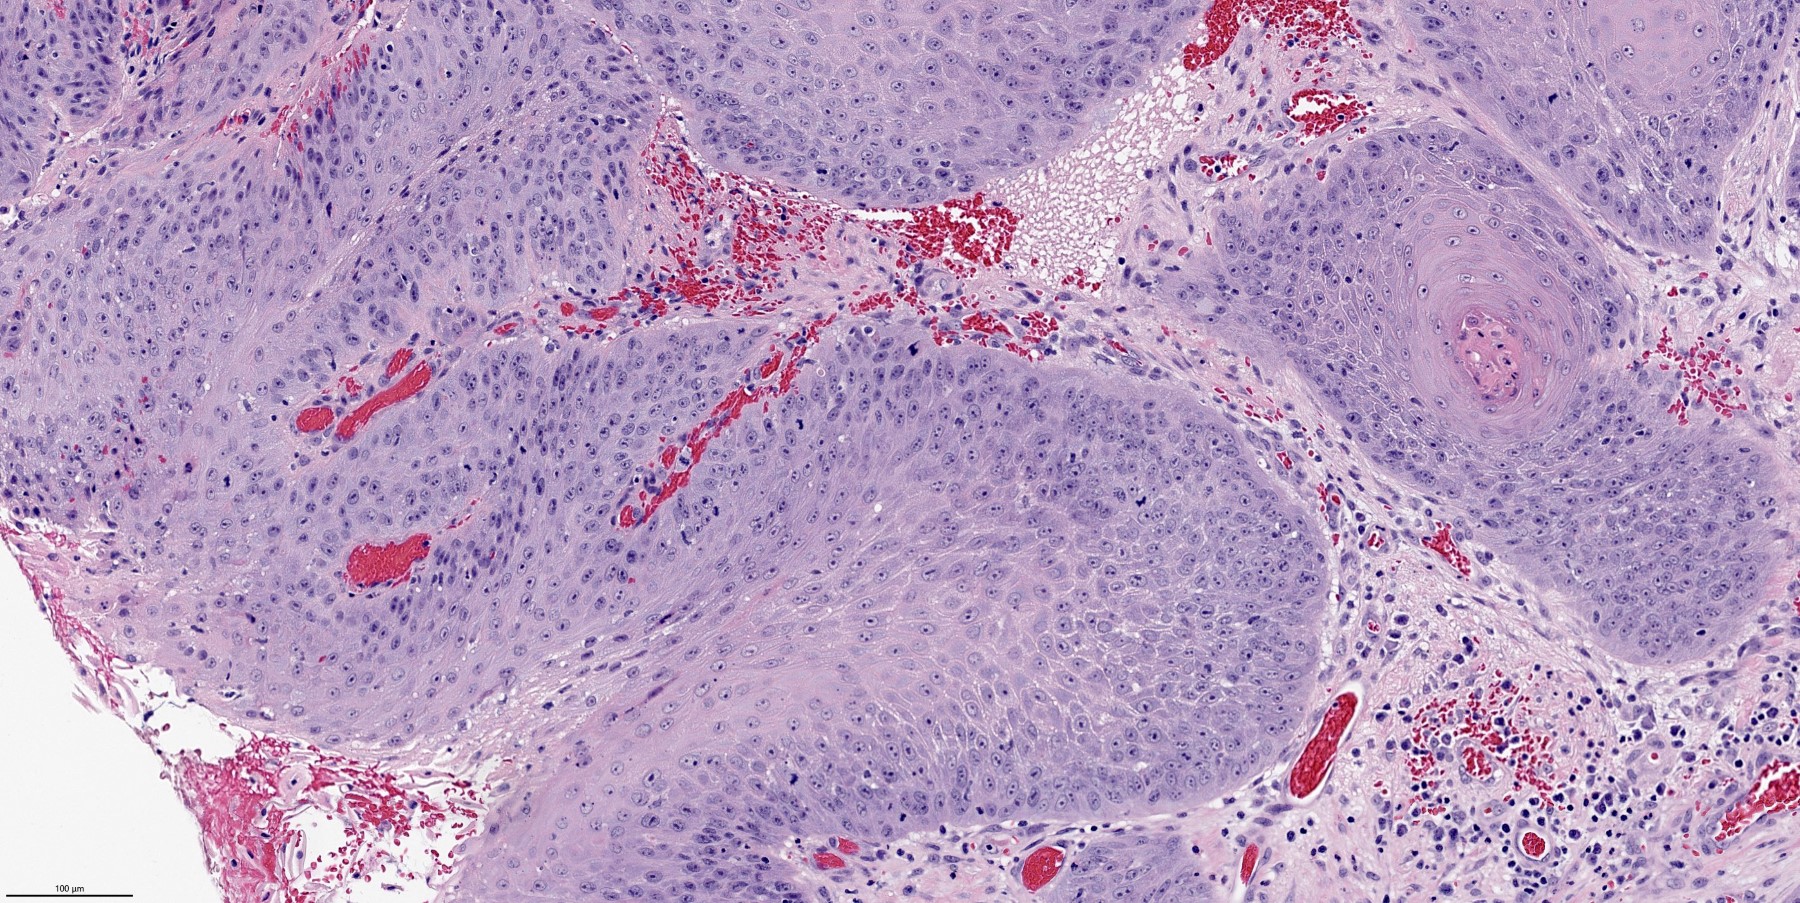

Microscopic (histologic) description

- Finger-like projections or multiple fronds with a central fibrovascular core, covered by benign hyperplastic stratified squamous epithelium

- Basal and parabasal hyperplasia

- Increased mitotic figures in the basal and parabasal layers

- Koilocytic changes in upper layer: may be pronounced or subtle

- Surface keratinization: absent to minimal

- Malignant transformation is characterized by aberrant (paradoxical) keratinization, marked cytological atypia, focal necrosis, increased mitoses and atypical mitoses not limited to the basal and parabasal layers, as well as invasive growth pattern (Respir Med 2017;126:116)

Microscopic (histologic) images

- Squamous cell carcinoma:

- Verrucous carcinoma and papillary squamous cell carcinoma may show verruciform or papillary architecture

- Verrucous carcinoma shows keratinization and broad pushing invasion

- Papillary squamous cell carcinoma shows marked cellular pleomorphism, full thickness mitotic activity and atypical mitoses